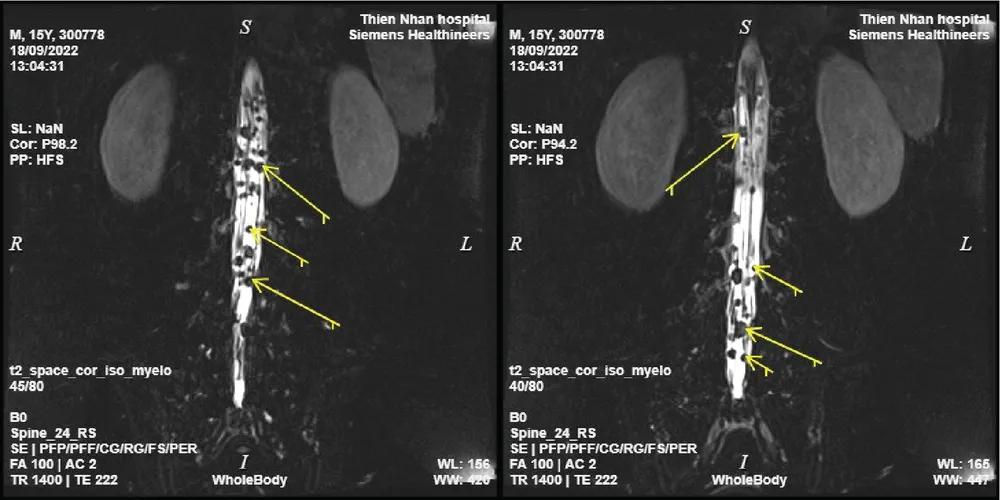

Rất nhiều nốt di căn ở đuôi ngựa và các rễ thần kinh đoạn trong ống sống |

Kết quả chụp MRI tại Thiện Nhân cho thấy khối u di căn nghiêm trọng đến tận vùng đuôi ngựa của tủy sống. Cùng thời điểm, có đoàn chuyên gia Hoa Kỳ về u não trẻ em đến làm việc tại Bệnh viện Phụ Sản - Nhi Đà Nẵng. Từ sự kết nối của Thiện Nhân, các cuộc hội chẩn liên tỉnh giữa các bác sĩ Thiện Nhân, các chuyên gia tại Hà Nội, TPHCM… và đoàn chuyên gia Hoa Kỳ diễn ra liên tục.

Kết luận cuối cùng ghi nhận chẩn đoán của Thiện Nhân là hoàn toàn chính xác, u tế bào mầm tuyến yên đã di căn đến tủy sống, cần được điều trị càng sớm càng tốt. Lập tức, các bác sĩ Thiện Nhân đã họp bàn và tư vấn với gia đình về nơi điều trị cho bệnh nhi. Sau gần 3 tháng với 4 đợt hóa trị, các bác sĩ tại Thiện Nhân nhận được thông báo hiện tại khối u đã không còn sau khi bệnh nhi chụp lại MRI não. Một kết quả đầy hy vọng và hạnh phúc cho em, cho gia đình và đặc biệt là đội ngũ y bác sĩ Thiện Nhân.